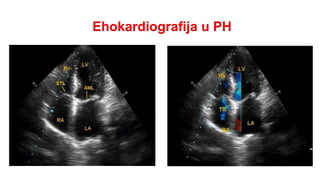

Ehokardiografija:

Transtorakalna ehokardiografija se koristi za uočavanje efekata PH na srce i procenu plućnog arterijskog

pritiska (PAP) kontinuiranim dopplerom. Za procenu lečenja PH nije dovoljna samo ehokardiografija već

se mora uraditi i kataterizacija desnog srca.

Najčešće Eho promene su:

Odnos bazalnog dijametra DK/LK >1,0

Zaravnjenje interventrikularnog septuma -indeks ekscentričnosti LK>1,1 u sistoli i/ili dijastoli

Vreme akceleracije RVOT <105 ms i/ili midsistolni zubac

Brzina rane dijastolne plućne reg. >2,2 m/s

Dijametar plućne arterije >25 mm

Dijametar VCI <21 mm sa smanjenim inspiratornim kolapsom (<50%)

Area DP (endsistolna) >18 cm²

Ehokardiografija u PH